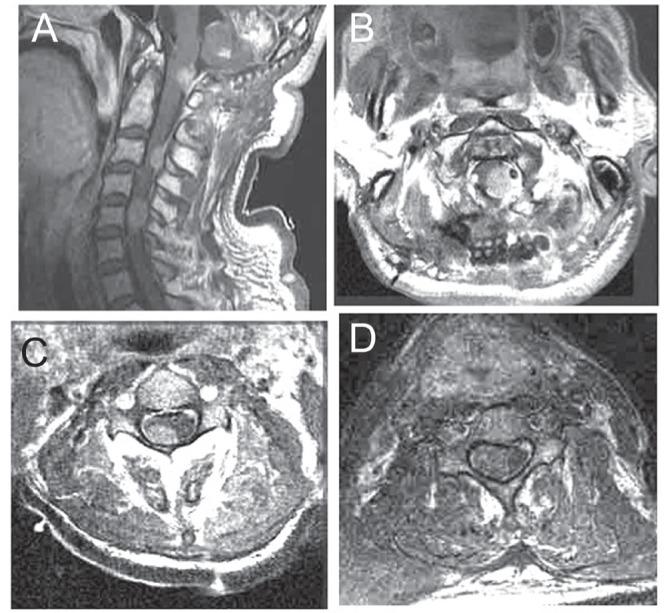

This report describes a rare case of a patient with growth hormone (GH)-secreting pituitary adenoma with malignant transformation resulting in multiple metastases to the dura mater of the cerebral convexity and high cervical spine. The patient was a 60-year-old man with a previous history of pituitary adenoma with suprasellar extension who had undergone transsphenoidal surgery, craniotomy for a convexity tumor, and suboccipital craniotomy for a cerebellar tumor. Thirteen years after the initial surgery, suboccipital craniotomy for a cervicomedullary junction tumor and cervicospinal surgery for a metastatic tumor was performed. Histologic findings of resected specimens demonstrated that the primary pituitary tumor was typical adenoma (similar to specimens from the initial surgery) but that the cerebellar and the dural tumor from the high cervical spine had a high incidence of mitotic figures, and cellular anaplasia with nuclear polymorphism and necrosis. In addition, the serum levels of GH were noted to have decreased with recurrence of the tumor. It was concluded that patients with pituitary adenoma, even when benign, must be carefully followed for signs of malignant transformation, and spinal or distant metastases.

本报告描述了一例罕见病例,患者为分泌生长激素(GH)的垂体腺瘤发生恶性转化,导致大脑凸面硬脑膜和高颈段脊柱多发转移。患者为一名60岁男性,既往有垂体腺瘤伴鞍上延伸病史,曾接受经蝶窦手术、凸面肿瘤开颅手术以及小脑肿瘤枕下开颅手术。初次手术后13年,因颈髓交界处肿瘤行枕下开颅手术,并因转移性肿瘤行颈脊髓手术。切除标本的组织学检查结果显示,原发性垂体肿瘤为典型腺瘤(与初次手术标本相似),但小脑和高颈段脊柱的硬脑膜肿瘤有较高的有丝分裂象发生率,以及伴有核多形性和坏死的细胞间变。此外,随着肿瘤复发,血清GH水平下降。得出的结论是,垂体腺瘤患者即使是良性的,也必须密切随访,观察有无恶性转化迹象以及脊柱或远处转移。